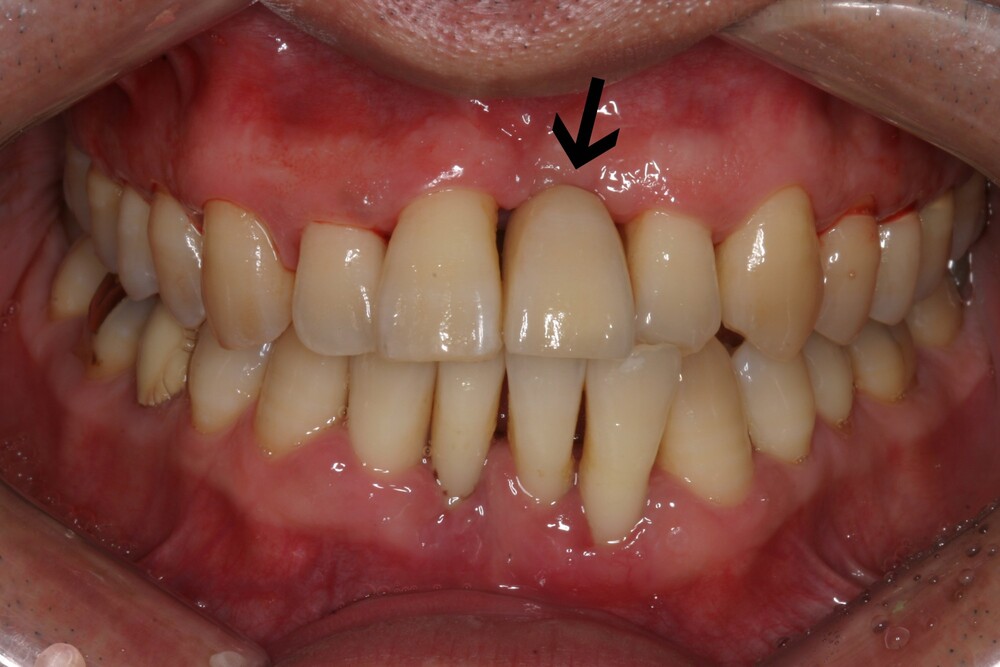

앞니의 경우는 어금니와는 달리 뼈가 얇아 치아를 뽑고 나면 뼈가 녹아서 푹 꺼져 버리게 됩니다.

발치 직후에 임플란트를 심어주게 되면 뼈와 잇몸모양 유지에 정말 도움이 됩니다. 마치 자연치아가 있는 것처럼 치료가 가능합니다.

(화살표의 치아가 발치 즉시 임플란트를 심어서 뼈와 잇몸모양을 유지한 사례)